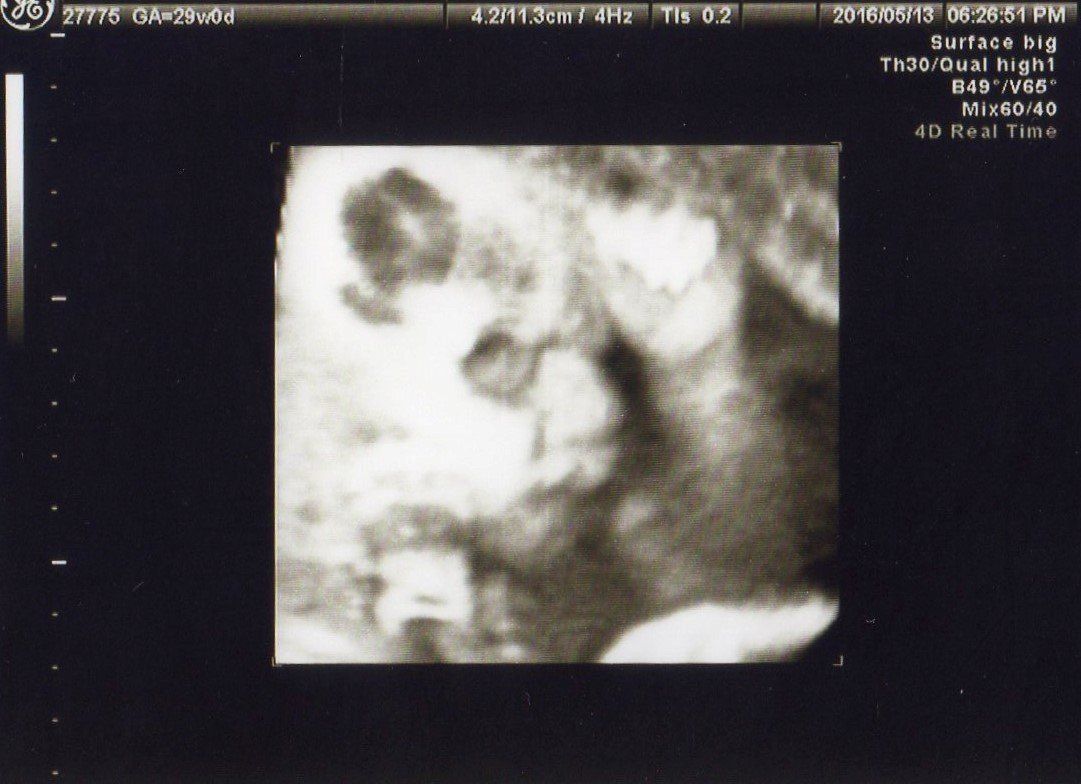

妊娠29週 推定体重が1000gを突破!

妊娠29週目の健診。赤ちゃんを真正面から見たエコー写真です。右上から斜めに頭・首・身体の順に見えます。EFW(胎児推定体重)がついに1000gを越えました!

胎動もだんだん活発になり、赤ちゃんの胎教に音楽を聴いたり、おなかを叩いて赤ちゃんと遊ぶ「キックゲーム」をしたり、いろいろと試しました。おなかにいる赤ちゃんとコミュニケーションがとれるなんて、不思議な気分でした。

これは同じ日の別写真。右から見た横顔になります。

左手を添えてなにか考えているようにも見えます。会うたびに違うポーズをとってくれる赤ちゃんがおもしろく、次の健診が待ち遠しくなりました。